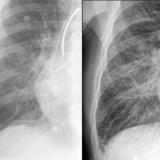

APE 4

Date: 11/05/2005

Views: 2825